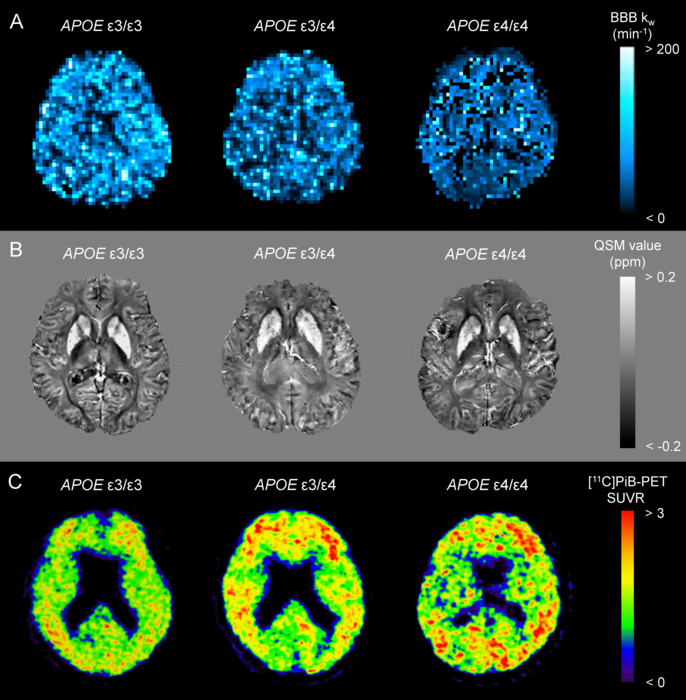

The current study aimed to verify the influence of APOE ɛ4 on effective BBB clearance, evaluated using an advanced magnetic resonance diffusion-prepared arterial spin labeling (DP-ASL) technique. An appealing feature of the DP-ASL technique is its non-invasive nature and ability to quantitatively estimate water exchange rate across the BBB (kw index) using a conventional 3.0-T MRI system.

First, we presented the clinical characteristics and neuropsychological scores for APOE ɛ4 noncarrier, heterozygous, and homozygous groups from the early stages of the Alzheimer's continuum cohort. Second, we compared AD-related imaging biomarkers, including the BBB kw map, quantitative susceptibility mapping (QSM), [11C]Pittsburgh compound B-positron emission tomography (PiB-PET), and cortical thickness. Finally, we assessed the correlation of kw values with neuroimaging metrics of AD pathology and neuropsychological scores. We concluded that APOE ɛ4 dose would be associated with poor brain-waste clearance through the BBB, causing brain iron and Aβ accumulation.